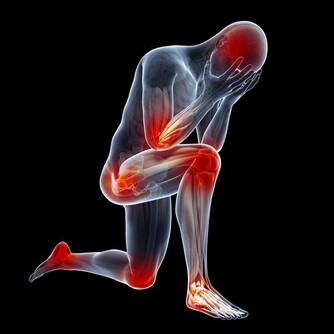

糖尿病的常見症狀包括,起夜次數頻繁、口乾、視力模糊、疲倦乏力、體重驟然下降、生殖器瘙癢、傷口所需的癒合時間過長等。這些都是身體無法正常分解血液中的葡萄糖所致。如果發現自己或家人朋友出現了類似狀況,要盡就醫治療。